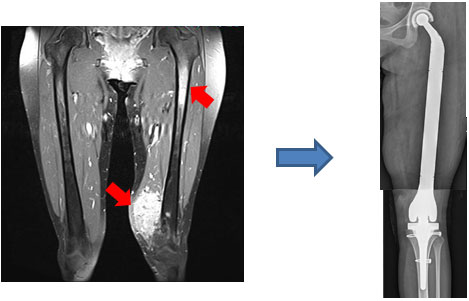

医師は滑膜肉腫の疑いがある場合、まずMRI スキャンを推奨します。この技術により、軟部肉腫の正確な画像を確実に生成できます。 MRI スキャンで腫瘍が検出された場合、医師は検査を続行できます。

NCIが説明しているように、最初の主要な治療法は手術です。手術は可能な限り腫瘍を切除し、がんの進行を遅らせることを目的としています。

医師は手術前または手術後に放射線療法を推奨する場合もあります。この技術は放射線を使用してがん細胞を死滅させます。